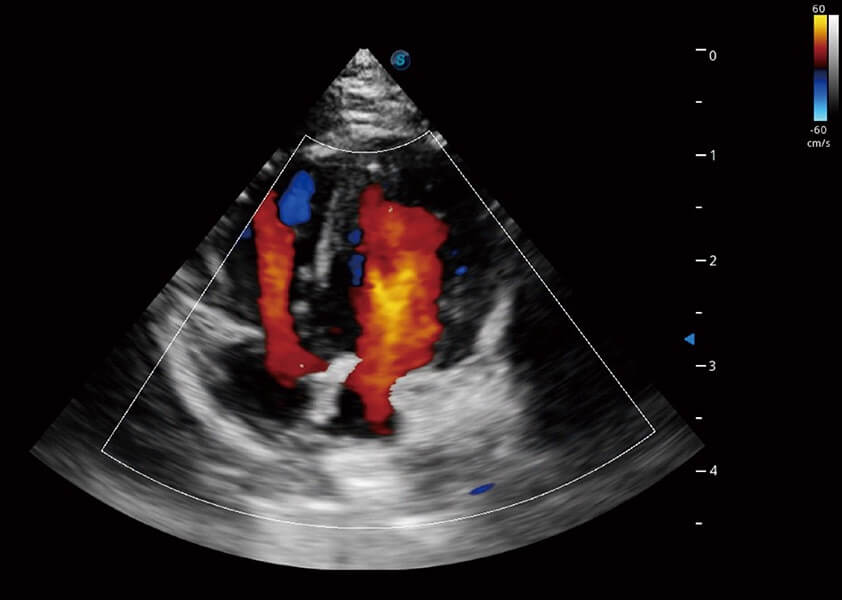

ProPet 60 作为一款高端台式动物超声设备,为动物医生的日常诊断提供了一系列贴合动物临床需求、解决临床实际问题的高级成像功能。凭借全系列高清探头,满足医生对腹部、心脏、生殖、浅表、肌骨等成像的所有需求,切实帮助您提升检查效率,提高诊断信心。

兽用彩色多普勒超声诊断系统

动物是人类最亲密的朋友和最值得信赖的伙伴。银河优越会也一直致力于探索动物专用的超声影像解决方案。 全新推出的ProPet系列,是银河优越会在动物超声影像智能化、专业化、精准化的一次跨越式革新。动物不能用言语来表述自己的不适,通过超声影像,ProPet系列搭建了动物医生与不同物种沟通的“桥梁”,为动物医生注入了“治愈之力”。